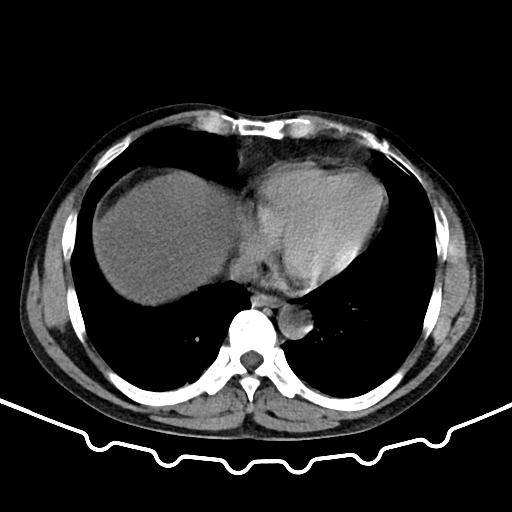

CT53610:女 50 腹痛 胰腺炎的那型,

女 50 腹痛 胰腺炎的那型, 平扫怎么区分水肿型与坏死型

胰腺明显肿大,实质内可见斑片状低密度区,边缘模糊不清,周边广泛蜂窝织炎及渗出性液性密度影,十二指肠升段及水平段受侵,支持急性坏死性胰腺炎。

重度脂肪肝,出血坏死性胰腺炎

胰腺轮廓不规则增大,与周围结构分界不清,内见斑片状高密度影及低密度混杂。部分见气泡影。胰周脂肪间隙模糊。双侧肾前筋膜增厚,右肾周及双肾前、后间隙、脾周、髂骨内侧面及腹部肠管积液。肝实质密度低,左肾囊肿。考虑:出血坏死性胰腺炎可能性大。

胰腺肿大,周围明显见渗出,小网膜脂肪层密度增高 不均匀。双侧肾前筋膜增厚,肾周脂肪模糊。诊断:急性胰腺炎—水肿型。

胰腺炎:1、轻者以胰腺水肿为主,临床多见,病情常呈自限性,预后良好,又称为轻症急性胰腺炎。

2、少数重者的胰腺出血坏死,常继发感染、腹膜炎和休克等,病死率高,称为重症急性胰腺炎。